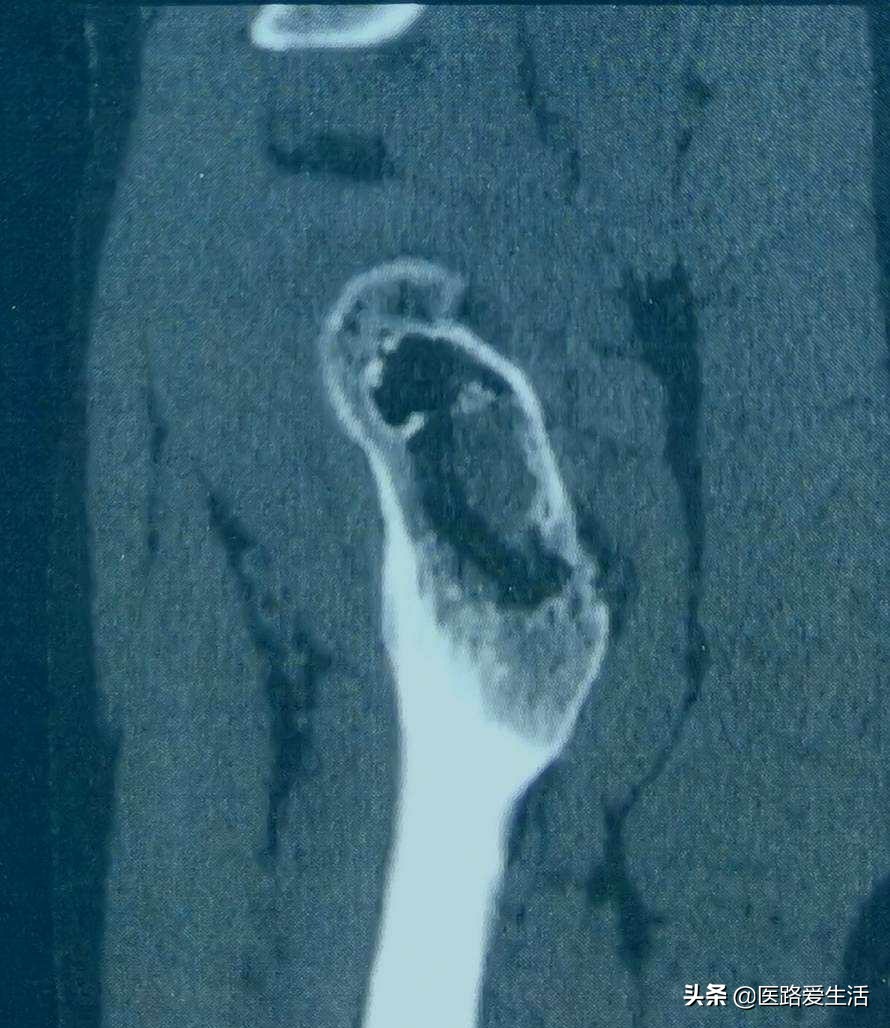

检查:1.最基本的X线检查可反应骨与软组织基本问题。

2.还有CT可提示病变的横断面影像。